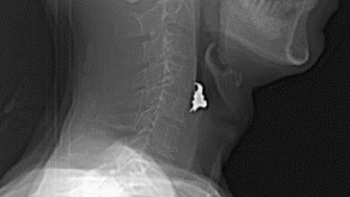

お薬のシート飲み込んだ・銀歯飲み込んだ・魚の骨が引っかかっている

検査

レントゲン CT

検査結果の例

[レントゲン]

白い三角形のようなものが「銀歯」

[CT]

白く細長く写っているものが「魚の骨」

病名

異物誤飲